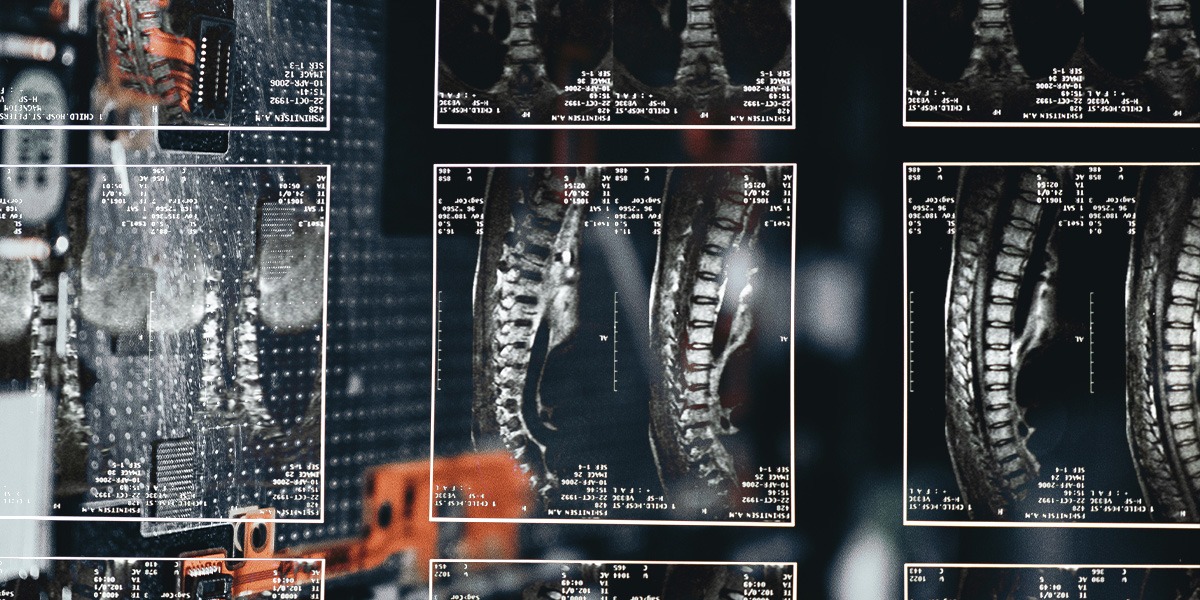

Az egészségügyi képalkotó technológia robbanásszerű fejlődése jelentős előrelépést hozott a betegségek feltárásában, a korai diagnózis felállításában, illetve a hatékony terápiák alkalmazásában. Kimutatások szerint a képalkotó vizsgálatok száma kétszer olyan gyorsan növekszik, mint az azt leletezni képes radiológusok száma, ezért világszintű probléma a szakemberhiány. Ezzel párhuzamosan rohamos ütemben fejlődnek az AI/MI rendszerek, melyek fokozatosan utat törnek magunknak az egészségügyi alkalmazásokban, valamint mindent átsző a digitalizáció, ami a lakosság digitális készségeinek, illetve a digitális információ felhasználására vonatkozó szolgáltatási folyamatoknak a fejlesztését teszi szükségessé. Az AUTORAD projekt által végrehajtott fejlesztés ezt a két irányt egyesítette magában azzal, hogy az automatikus leletezésen keresztül olyan digitális felületet hozott létre, ahol a páciens és orvos közötti együttműködés (ügyfélélmény), ezzel együtt az ellátás minősége és kimenete is javulhat, magasabb egészségértéket biztosítva. Az AUTORAD projekt keretében többek között az orvos-beteg kommunikáció eredményességének javítása céljából egy vizualizált gerinc MR lelet megjelenítő rendszer, valamint egy intelligens leletkezelő alkalmazás megvalósítására került sor. A projekt ezen felül kiindulópontként szolgálhat az orvoshiány, különösen radiológusok hiányának kérdéskörében is. Az AUTORAD automata gerinc MR leletező alkalmazás intelligens megoldásként szolgálhat a kézi leletezés felgyorsítására, valamint pontosabb diagnózis felállítására.

A projekt végtermékei között szerepel egy több 10.000 gerinc MR vizsgálat automatikus feldolgozásán alapuló intelligens adatbázis, egy intelligens leletkezelő alkalmazás, egy automatizált radiológiai lelet-értelmező applikáció, ami egy 2D vizualizációval támogatott intelligens lelet, valamint egy automata gerinc MR leletező mesterséges intelligencia algoritmus és applikáció, ami a meglévő PACS szerverekhez kapcsolódva, a gerincről készült MR vizsgálatok automatizált leletezését végzi.